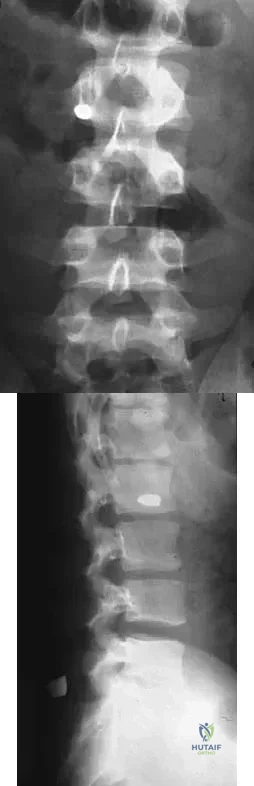

Question 19

A 25-year-old man has had an insidious onset of left hip pain over the past 11 months. A radiograph, coronal MRI scan, and histopathologic specimens are seen in Figures 2a through 2d. What is the most likely diagnosis?

Explanation